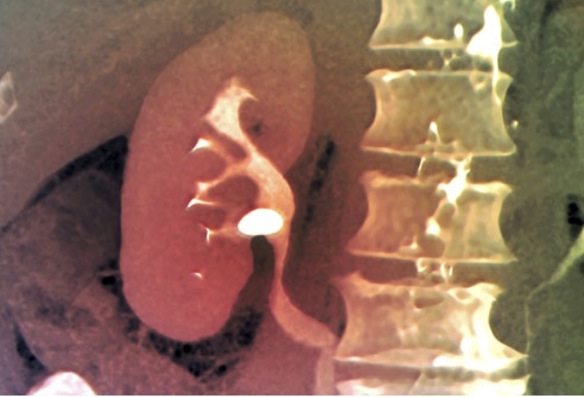

Para confirmar el diagnóstico se emplean pruebas de imagen, que nos permiten confirmar la existencia, tamaño y localización de las litiasis. La ecografía es el medio más empleado, muchas veces acompañada de radiografías con/sin contraste (urografía intravenosa o TAC). En ocasiones son necesarias analíticas complementarias o endoscopias.

La orina contiene cristales disueltos, que en determinadas circunstancias pueden reunirse para formar una masa sólida, que se denomina cálculo o litiasis. Si este cálculo obstruye el interior de la vía urinaria, impidiendo el libre curso de la orina, provoca un dolor muy intenso denominado cólico nefrítico, y sangrado por la orina.

Lós cálculos urinarios más frecuentes están formados por cristales de calcio (oxalato, fosfato), ácido úrico, cistina y fosfato amónico magnésico.